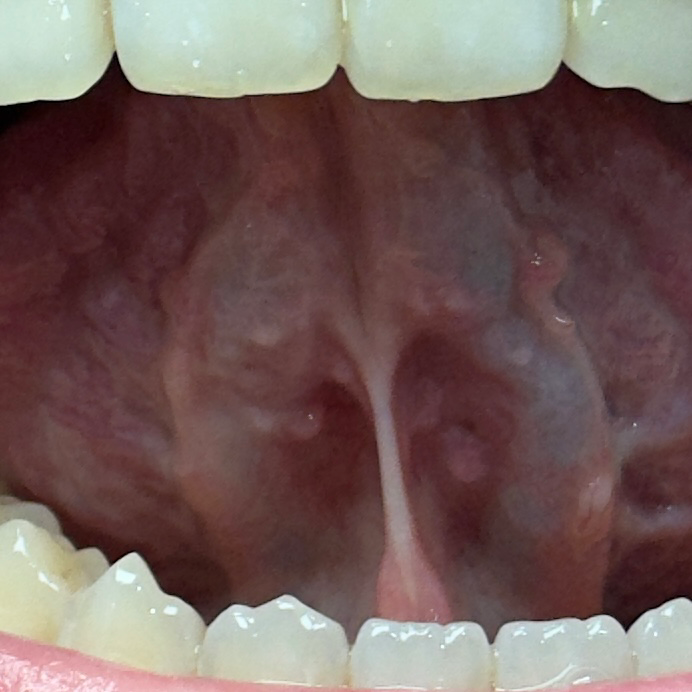

혀 아래,밑부분에 돌기?뾰루지? 같은게 있습니다

혀 밑부분에 돌기나 뾰루지 같은게 있는데요.

(사진은 좀 흐릿하게 나온편입니다)

예전부터 있었는지,최근에 생긴건지는 모르겠습니다.

1. 병원에 꼭 가봐야 하는 질병일까요??

2.악성 종양일 가능성이 있을까요??

• 2번 째 사진